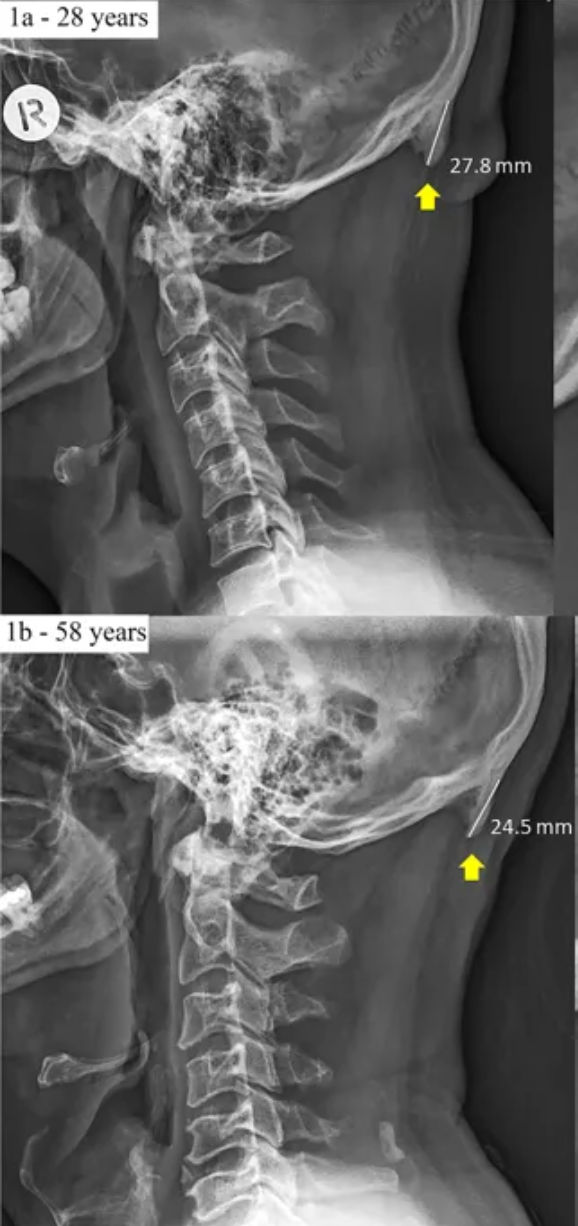

New research in biomechanics suggests that young people are developing hornlike spikes at the back of their skulls — bone spurs caused by the forward tilt of the head, which shifts weight from the spine to the muscles at the back of the head, causing bone growth in the connecting tendons and ligaments. The weight transfer that causes the buildup can be compared to the way the skin thickens into a callus as a response to pressure or abrasion.

The phenomenon is called an EEOP, or enlarged external occipital protuberance, and in a study of 1200 people, they found that about a third have this feature…and that it is more common in men and younger people. They assume from the differences in frequency at different ages that this is an emerging, recent change, which may be reasonable, but I’d like to see a better analysis of the causes.